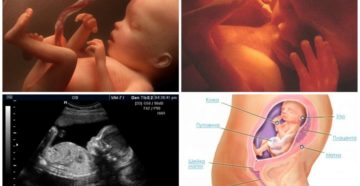

23 неделя беременности Зачатие и развитие эмбриона представляет собой длительный и захватывающий процесс, приводящий в…